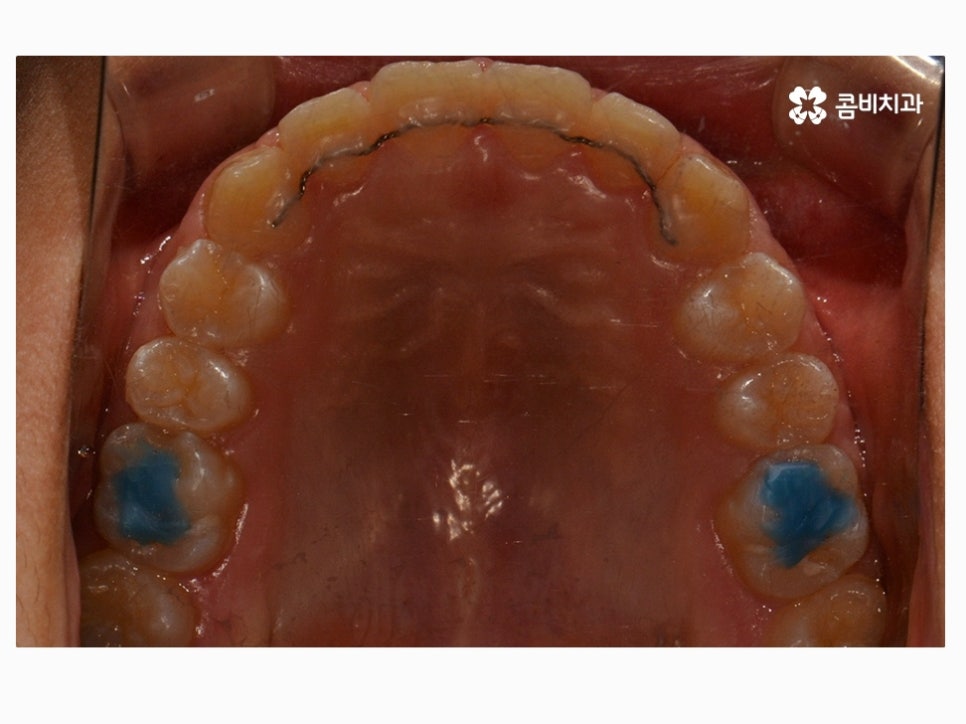

위 환자분께서 사용하신 장치는 클리피씨로 자가 결찰 장치이며

초기 통증이 줄어들고 관리가 용이하며 시술 기간을 단축시킬 수 있다는 장점이 있어요.

요즘은 이처럼 세라믹 재질을 활용하여 심미성은 높이고

교정 과정이 보다 효율적인 장치가 많이 사용되고 있는데요.